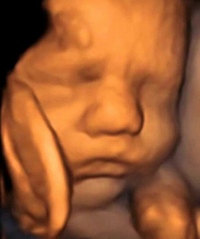

• Ecografía con translucencia nucal

• Ecografía obstétrica